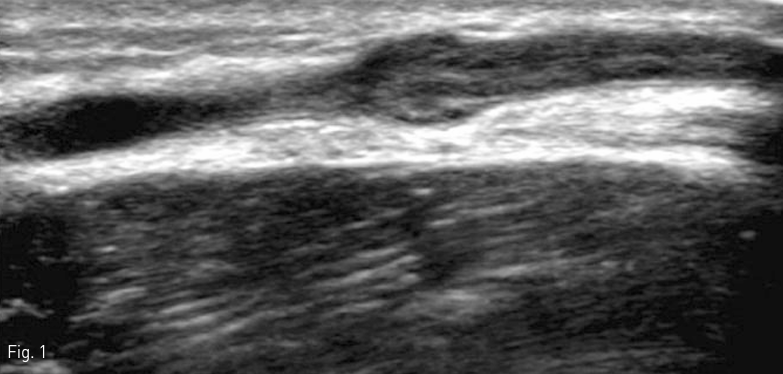

오른쪽 전완부 초음파 검사에서 환자가 압통 및 발적을 호소한 부위에는 피하부종이 보였다. 색 도플러 검사에서는 이 부위에 늘어난 팔 오금 중간 정맥 (median cubital vein) 이 보였고, 정맥 내에 긴 분절 형태의 고 에코 혈전이 있었다 (Fig. 1). 늘어난 팔 오금 중간 정맥에 정맥 혈류는 전혀 보이지 않았다 (Fig. 2). 그 외의 자쪽 피부 정맥 (basilic vein), 노쪽 피부 정맥 (cephalic vein), 그리고 심부 정맥 (deep vein)들 내에는 혈전은 보이지 않았고, 정상 혈류가 유지되고 있었다.

Fig 1

Ultrasound of the right forearm demonstrates a dilated median cubital vein with internal hyperechoic thrombus.